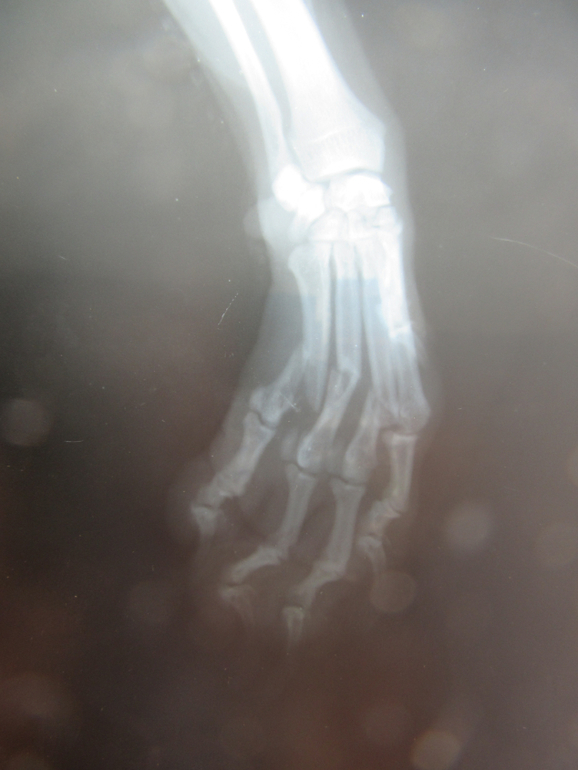

Полный перелом 3,4,5 пястных костей со смещением передней лапы у собаки

Перелом случился по вине моей и мужа,понятно было сразу,что лапе п.здец,собака очень плакала.Сразу же муж повез Варю в ветеринарку,откуда его направили на рентген на Кр.Путь 139 б клиника "Биота".Сделав снимок выдали заключение "Полный перелом 3,4,5 пястных костей со смещением передней левой лапы".Время шло к закрытию.Муж шокирован,ему что-то обьясняют врачи,он сказал что мало что понимал от состояния своего.Сказали сразу-операция,стоимость 10 т.р.Сутки на подумать.Не понимаю почему муж сразу же не записался на операцию,меня не было с ним.Пока он ехал я обзванивала беспощадно закрывающиеся ветклиники......Многие этим не занимаются,а другие говорят "Приходите,консультация 500 р,а там будем решать гипс или операция".ШТЭ???????????Какой нахер гипс,бля?????????Бегите из клинике,если озвучив такой диагноз вам говорят про гипс!!!!Собака лежала весь вечер и всю ночь на месте,передвигалась по надобности на 3 лапах.Я твердо решила,что врачи в клинике Биота адекватные,вынесли верное решение,вставлять штифты.

Фото что было и что стало.

Следующий день опухоль уже спала совсем,лапа как остальные по размеру.Пытается наступать на лапку все больше.